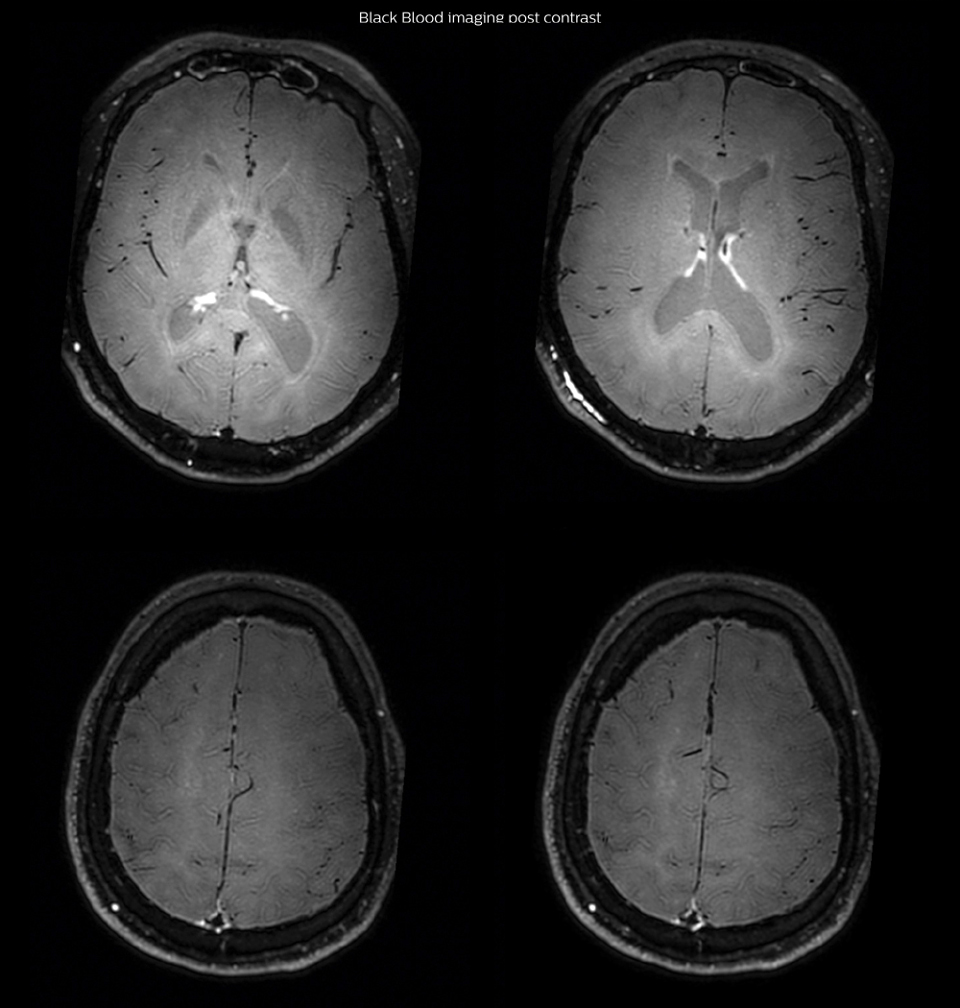

On FLAIR images we can see some nonspecific high signal abnormalities in frontal white matter bilaterally. On DWI we can see acute ischemic lesions which appear with high signal intensity. Arrows show vessel wall enhancement which appears concentric and homogeneous in different cerebral territories.

After one month of treatment, post-contrast Black Blood images at the exact same levels as in the figure above show disappearance of the vessel wall enhancements which were seen on the previous examination.